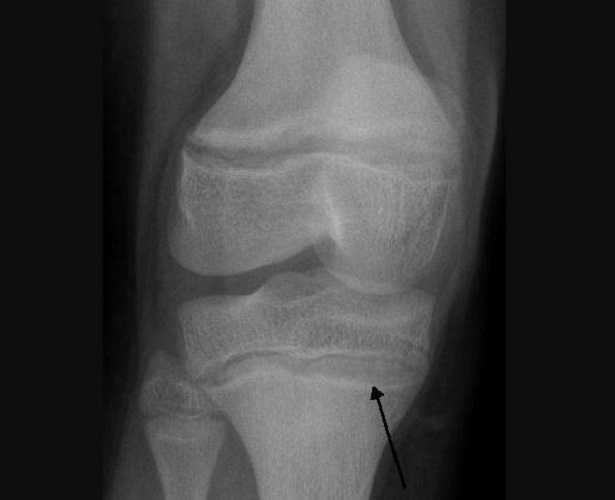

L’anemia è uno dei sintomi del saturnismo, magari non il più diffuso ma nemmeno il più raro. Quando il piombo viene assorbito, si distribuisce in larga parte negli eritrociti e solo in minima parte nel plasma per poi arrivare ai tessuti molli, alle osso e a capelli e denti. L’anemia che deriva da questo tipo di intossicazione si chiama anemia ipocromica, chi ne soffre produce globuli rossi alterati, definiti “punteggiati”.